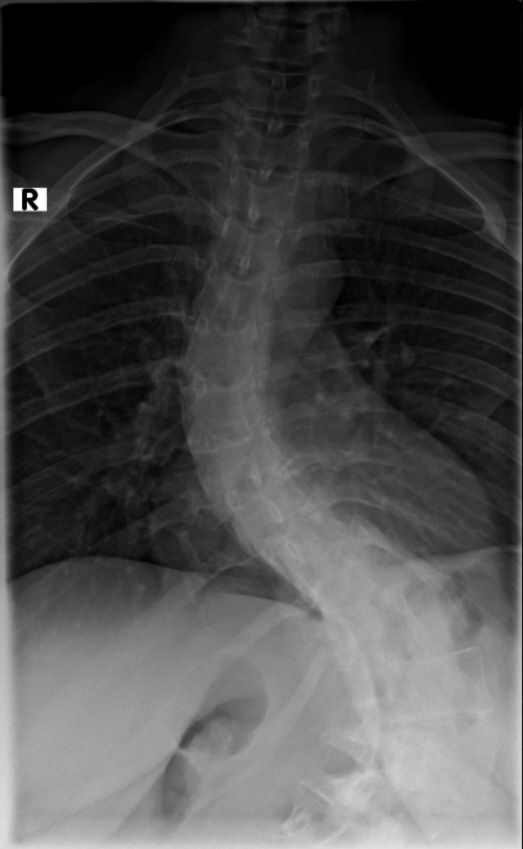

Diagnose: Thorakolumbalskoliose - Cobb-Winkel 60 und 80

Thorakolumbalskoliose mit aktuellen COBB-Winkeln von 80 und 60 Grad...wenig Schmerzen und daher meistens glücklich :D .

Viele kennen sich aus, daher möchte ich euch meine aktuellen Röntgenbilder nicht vorenthalten und hänge sie unten an.

Ich war beim MVZ Gersthofen, dort wurden die Röntgenbilder gemacht…die massive Verschlechterung war sehr offensichtlich :( , drum wurde ich gleich an die Experten zur Hessing Klinik überwiesen.

Dort wurden die Winkel gemessen, unten 80 Grad und oben 60 Grad…eine Verschlechterung von über 2 Grad pro Jahr, wenn man es auf die ganze Zeit berechnet :( .

2021-09-09_Unten_von_der_Seite.jpg

(136.54 KiB) Noch nie heruntergeladen